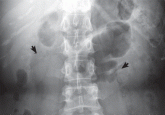

ArticleRecurrent pyelonephritis as a sign of ‘sponge kidney’Author:Ming-Tso Yan, MDPublish date: August 1, 2009Intravenous urography is the gold standard for the diagnosis of medullary sponge kidney. Computed tomography and ultrasonography have limited abili...Read More